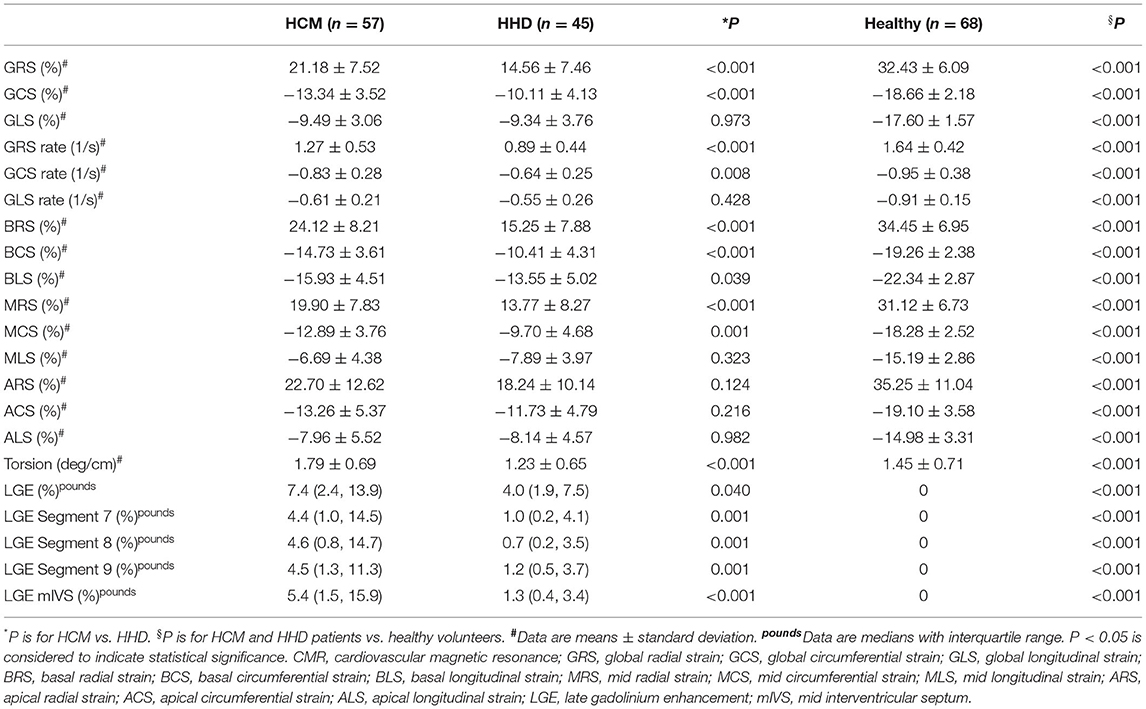

Global radial strain (GRS) and global circumferential strain (GCS) were significantly higher in the HCM group relative to the HHD group, as shown in Table 2 (GRS, 21.18 ± 7.52 vs. 14.56 ± 7.46%; GCS, −13.34 ± 3.52 vs. −10.11 ± 4.13%; both P < 0.001), whereas comparisons of GLS showed no obvious difference (−9.49 ± 3.06 vs. −9.34 ± 3.76%, P = 0.973). Similar trend could also be detected in corresponding strain rate.

As for segmental strain analysis, the three basal parameters [which included basal radial strain (BRS), basal circumferential strain (BCS), and basal longitudinal strain (BLS)] were higher in the HCM group than in the HHD group (BRS, 24.12 ± 8.21 vs. 15.25 ± 7.88%; BCS, −14.73 ± 3.61 vs. −10.41 ± 4.31%; BLS, −15.93 ± 4.51 vs. −13.55 ± 5.02%; all P < 0.05). Mid-radial strain (MRS) and mid-circumferential strain (MCS) were also higher in patients with HCM relative to patients with HHD (MRS, 19.9 ± 7.83 vs. 13.77 ± 8.27%; MCS, −12.89 ± 3.76 vs. −9.7 ± 4.68%; both P < 0.05), but mid-longitudinal strain (MLS) had no significant difference between the two groups. None of the three apical strain results showed obvious differences between the HCM and HHD cohort. Torsion in the HCM group was higher than that in the HHD group (1.79 ± 0.69 vs. 1.23 ± 0.65 deg/cm, P < 0.001).

Late gadolinium enhancement was assessed in 170 participants and shown in Table 2. Healthy subjects presented no LGE. Patients with HCM in comparison to patients with HHD had higher values of LGE (total enhanced volume percentage) (P < 0.05). On segmental analysis, the differences in LGE values were predominantly localized around the interventricular septum (segments 7, 8, and 9; all P = 0.001), which corresponds to the mid-segment of the anterior, anteroseptal, and inferoseptal of IVS. It was also pronounced for mIVS (P < 0.001) (Figure 2), but there were no significant differences in other segments.